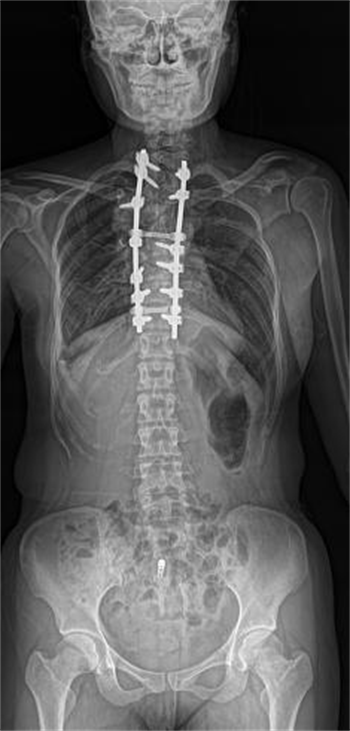

左为二维平片,右为LF-TOMO图像

不仅如此,在图像质控方面,安健科技自主研发的高空间分辨率平板探测器与先进图像处理技术的结合,使得LF-TOMO大范围断层融合技术可以提供高清晰度的断层图像,对于微细骨折的诊断等方面可以提供有效评估。另一方面,LF-TOMO断层融合图像不受体位及金属植入物的影响,无重叠组织结构及金属伪影的干扰,空间分辨率高,为诊断医生提供更多的影像学信息,以提高对病灶的检出率和准确率。因此,LF-TOMO大范围断层融合技术在骨科,对于金属植入物患者的随诊观察有很好的效果,辅助医生完成术前诊断、术中定位以及术后评估。